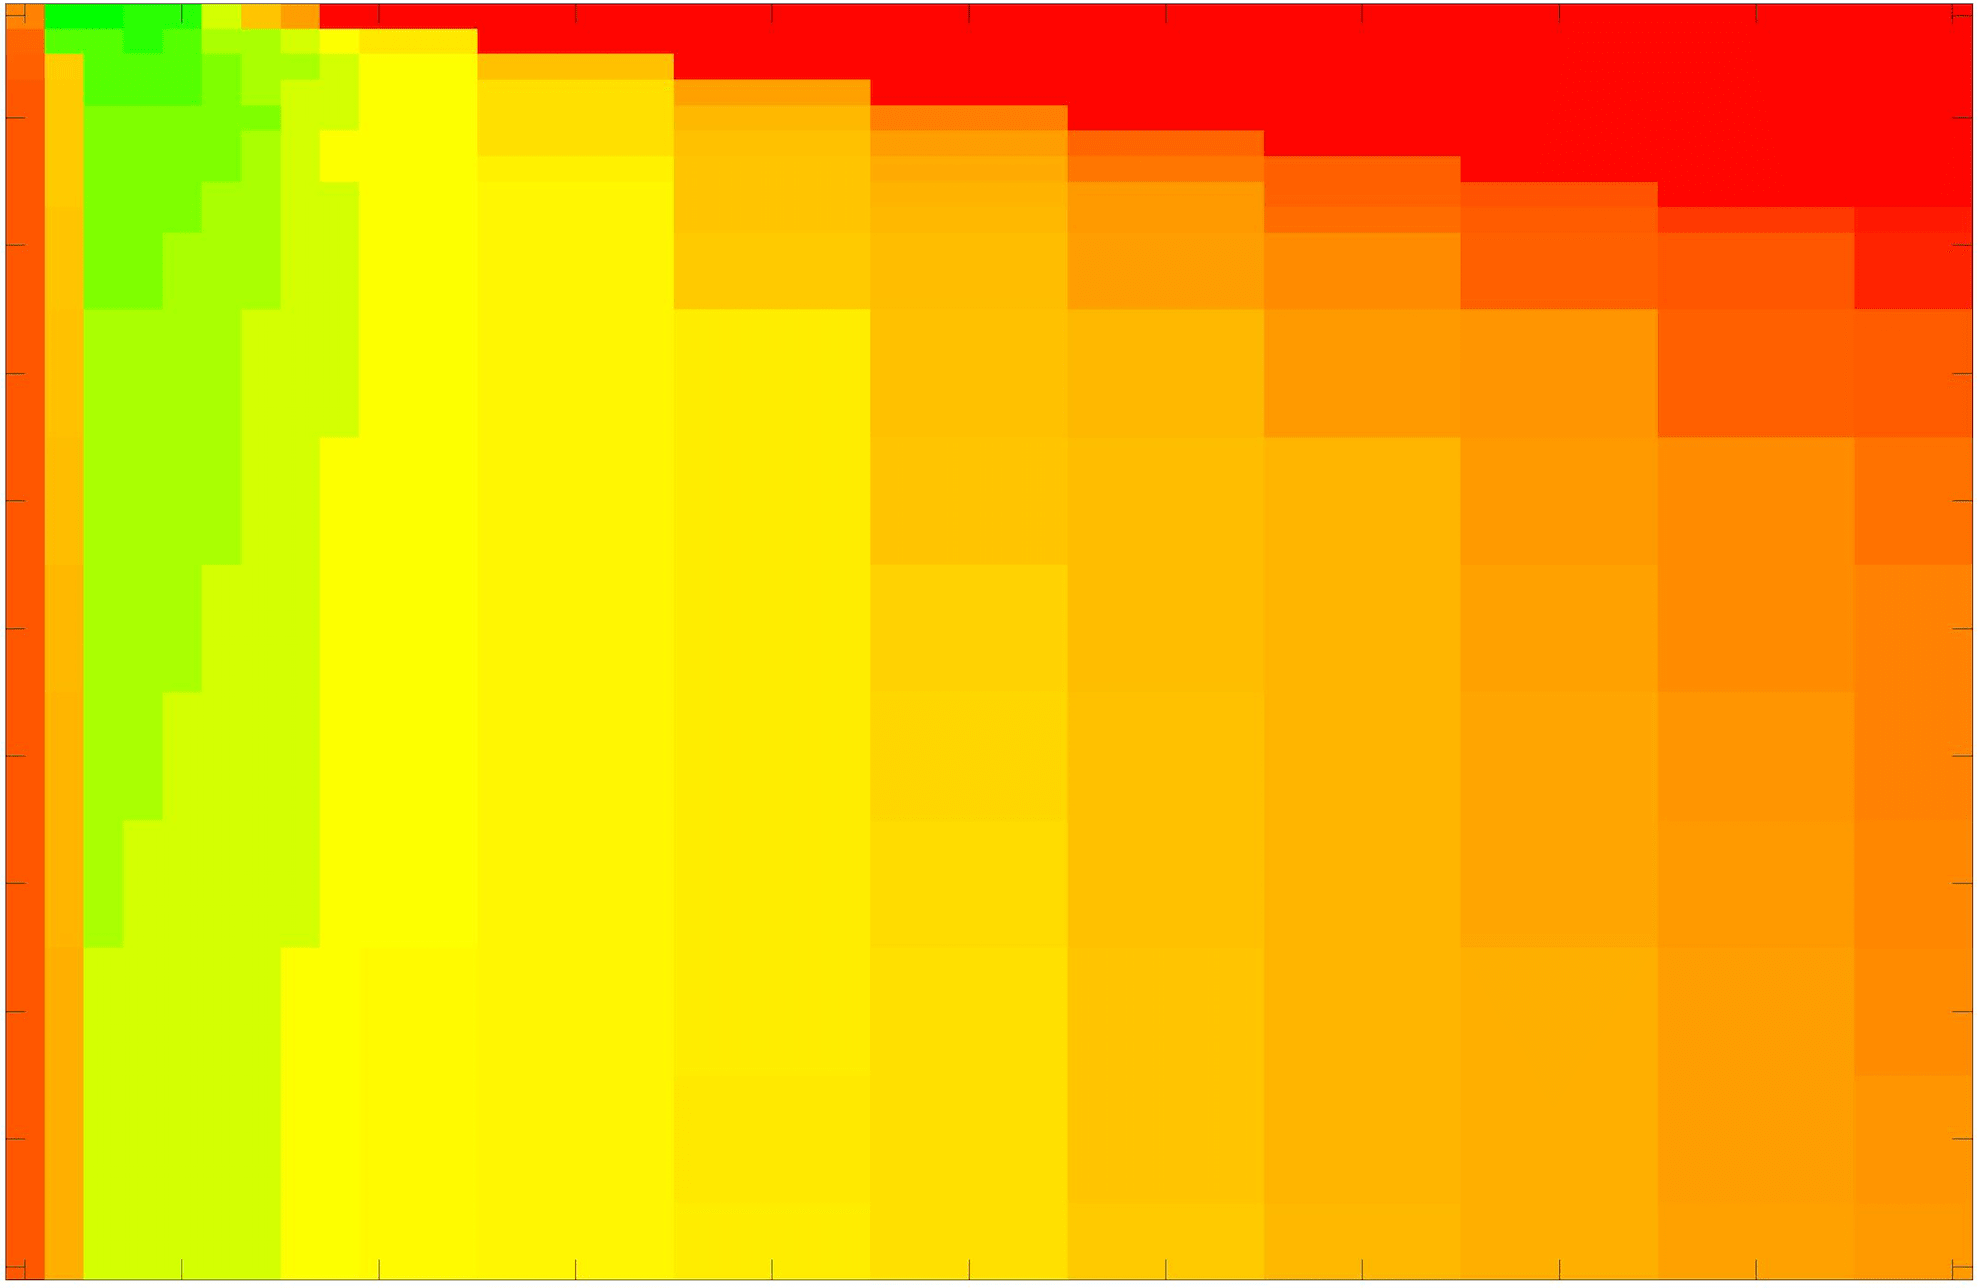

In these tests we aim to demonstrate how sensitive to parameter choices each choice of fitting term is. To accomplish this we perform the segmentations for each of the models discussed (CV, RSF, LCV, HYB, GAV) and the proposed model for a wide range of parameters and compute the TC value. The parameter range used is . Due to computational constraints, we run for each integer between 1 and 10, and every fifth from 15 to 50. This aspect of a model’s performance is vital when used in practice. The less sensitive to parameter choices a model is the more relevant it is in relation to potential applications. It should be noted that we neglect to test the selective models detailed in §3 with respect to parameter robustness as we are using the authors’ implementation of each approach. Instead, we make direct comparisons in the following sections.

The TC values for the parameter sets are presented as heatmaps in Figs. 11–13. A heatmap is a convenient way to display accuracy results for hundreds of tests concisely. In Fig. 9 we give an example heatmap with the same axes used for those in Figs. 11–13. For each of the combinations of parameter values we give the TC value of the segmentation result and represent it by the appropriate colour. The corresponding colour scale is shown in Fig. 8. Qualitatively, the more green areas of the heatmap the more accurate the model is for a wider set of parameters. Example results for Test Image 5 when varying (with ) for the proposed model are given in Fig. 10. Here it can be seen what each accuracy result corresponds to visually.

Note. The axes have been removed from the heatmaps in Figs. 11–13 for presentational clarity. However, to be explicit, the axes used in all heatmaps are the same as those in Fig. 9.

Real Images. In Fig 12 we present results for Test Images 4–6. Here, the proposed model performs in a similar way to its competitors because these images are more typical selective segmentation problems in the sense that there is a clear distinction between the foreground and background intensities. In particular, the values in each case are: Test Image 4 , Test Image 5 , and Test Image 6 . It can be seen that the proposed model is competitive compared to previous approaches. The performance is quite poor for Test Image 5, but is arguably still the best for this challenging case. In Fig. 13 we present results for Test Images 7–9. Here the proposed model outperforms previous approaches significantly for each image. This is mainly due to the type of image considered. Specifically, the true intensities are: Test Image 7 , Test Image 8 , and Test Image 9 . The proposed model is capable of achieving results where , with other models failing completely in these cases.